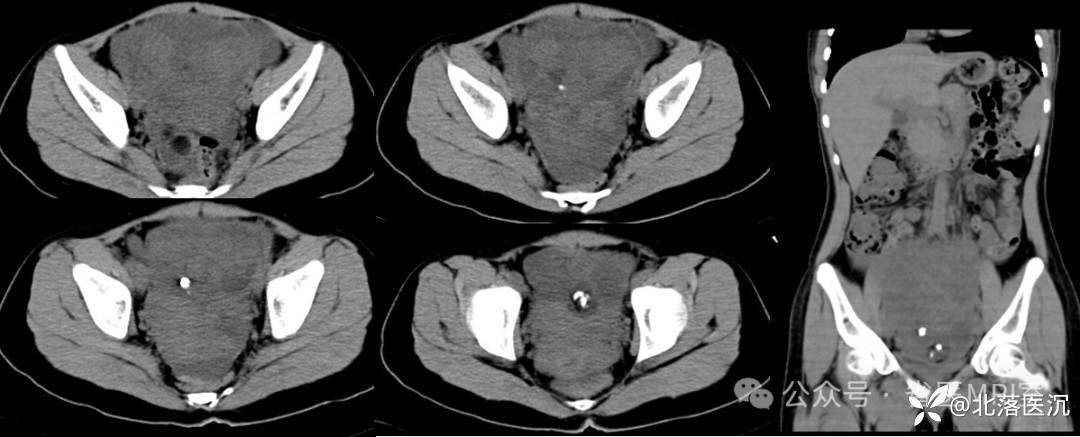

影像学表现:

双侧附件区可见巨大囊性包块影,最大截面大小约203X119mm,98x95mm,囊液密度均匀,未见明显分隔,病变左侧可见斑片状脂肪密度影及结节状钙化影,边界清楚,下方小病变内见脂液平面,周围肠管及子宫受压移位。腹膜后主动脉旁及升结肠周围脂肪间隙内见多发肿大淋巴结,较大者短径约10mm。

1、双侧附件区占位,考虑囊性畸胎瘤可能,畸胎瘤继发浆液性囊腺瘤待除外,建议MRI增强检查;

病理学诊断:成熟性囊性畸胎瘤